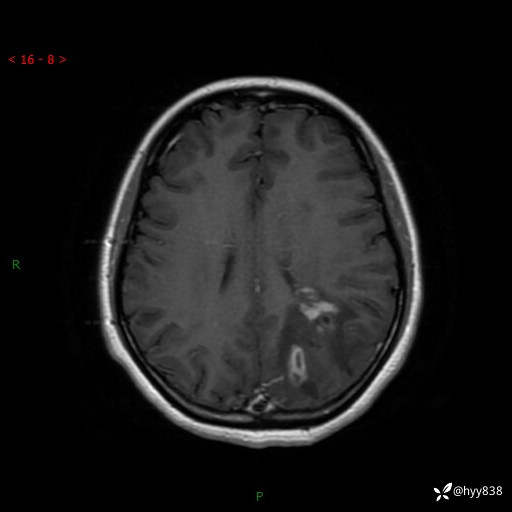

颅脑MRI平扫+增强